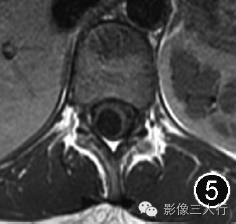

图4~7 男,45岁。腰椎MRI显示第五脑室是位于脊髓圆锥内且囊壁光滑的囊腔,囊腔内的脑脊液在矢状面T1WI上呈低信号(图4),在横断面T1WI上呈低信号(图5),在矢状面T2WI上呈高信号(图6),在横断面T2WI上呈高信号(图7)。所有图片均由加拿大渥太华大学渥太华医院Carlos Torres教授提供